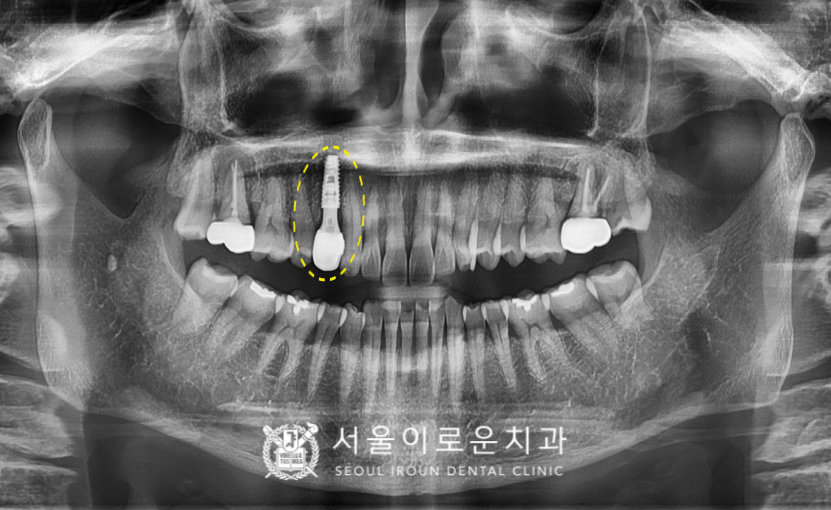

오늘 소개해 드릴 분은 60대 여성분으로,

오른쪽 위 송곳니 쪽에

딱딱한 음식을 먹었는데

치아가 갈라져서 흔들리며,

아프시다며

본.원을 찾아주셨습니다.

확인해 보았더니

노란색 동그라미 표시의

오른쪽 위 첫 번째 작은 어금니(#14)에서

불편감을 보이셨는데요.

x-ray 상으로는 크랙 라인이

또렷하게 관찰되지는 않지만

구내에서 확인하였을 때

상당히 깊게 크랙이

진행된 것으로 보였으며

타진 반응에도 통.증이 있었습니다.

안타깝게도 치아가 둘로 쪼개져

예후가 좋지 않아

발치를 해야 하는 상황이었답니다. (ㅠㅠ)